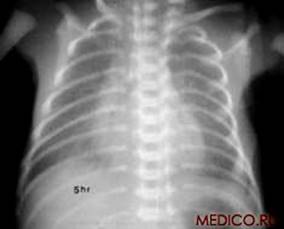

А) Б)

Рис 1. Рентгенограммы легких: а) взрослого мужчины; б) ребенка.

При рентгенологическом исследовании грудной клетки ясно видны два светлых «легочных поля», по которым судят о легких, так как вследствие наличия в них воздуха они легко пропускают рентгеновские лучи и дают просветления. Оба легочных поля отделены друг от друга интенсивной срединной тенью, образуемой грудиной, позвоночником, сердцем и крупными сосудами. Эта тень составляет медиальную границу легочных полей; верхняя и латеральная границы образованы ребрами. Снизу находится диафрагма.

Верхняя часть легочного поля пересекается с ключицей, которая отделяет надключичную область от подключичной. Ниже ключицы на легочное поле наслаиваются пересекающиеся между собой передние и задние части ребер. Они располагаются косо: передние отрезки – сверху вниз и медиально; задние – сверху вниз и латерально. Хрящевые части передних отрезков ребер при рентгеновском исследовании не видны. Для определения различных пунктов легочного поля пользуются промежутками между передними отрезками ребер (межреберья).

Собственно легочная ткань видна в светлых ромбовидных межреберьях. В этих местах виден сетевидный или пятнистый рисунок, состоящий из более или менее узких тяжеобразных теней, наиболее интенсивных в области корней легких и постепенно убывающих в своей интенсивности от срединной тени сердца к периферии легочных полей. Это так называемый легочный рисунок. По обе стороны тени сердца на протяжении передних отрезков II – V ребер располагаются интенсивные тени корней легких. От тени сердца они отделены небольшой тенью главных бронхов. Тень левого корня несколько короче и уже, так как она больше прикрывается тенью сердца, чем справа.

Анатомической основой тени корней и легочного рисунка является сосудистая система малого круга кровообращения – легочные вены и артерии с радиарно отходящими от них ветвями, рассыпающимися в свою очередь на мелкие веточки. Лимфатические узлы в норме не дают тени.

Анатомический субстрат легочного рисунка и теней корней особенно ясно заметен при томографии (послойной рентгенографии), которая дает возможность получить снимки отдельных слоев легкого без наслоения на легочное поле ребер. Легочной рисунок и корневые тени есть симптом нормальной рентгеновской картины легких в любом возрасте, включая и ранний детский. При вдохе видны просветления, соответствующие плевральным синусам.

Рентгенологический метод исследования позволяет видеть изменения в соотношениях органов грудной клетки, происходящие при дыхании. При вдохе диафрагма опускается, куполы ее уплощаются, центр передвигается несколько книзу. Ребра поднимаются, межреберные промежутки делаются шире, Легочные поля становятся светлее, легочный рисунок отчетливее. Плевральные синусы «просветляются», становятся заметными. Сердце приближается к вертикальному положению. При выдохе возникают обратные соотношения.